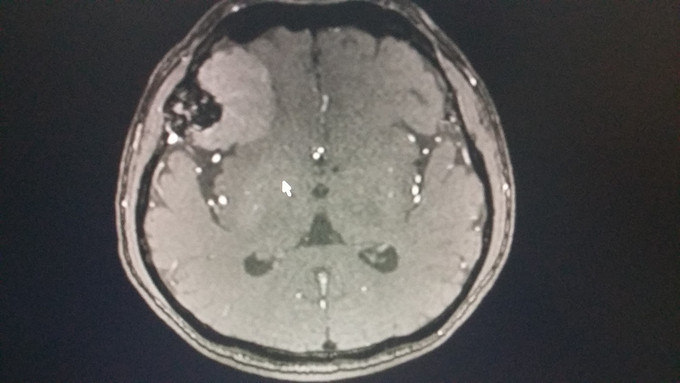

1、患者 男 67岁 体检发现颅内占位病变2月,右侧肢体麻木、头晕10天;既往有高血压病史 2、患者2月前体检行头颅CT检查发现右侧脑膜留,未做特殊处理,10天前无明显诱因出现右侧肢体麻木,头晕,饮水呛咳,口水及吃饭难于下咽,到当地医院就诊查头颅MRI:右侧蝶骨脊脑膜瘤可能,延髓偏左侧出血,海绵状血管瘤可能。

3、神清,伸舌居中,咽反射双侧消失;四肢肌力5级,右侧肢体感觉减退 4、头颅MRI:右侧蝶骨脊脑膜瘤可能,延髓偏左侧出血,海绵状血管瘤可能

5、入院诊断:1.右侧蝶骨脊脑膜瘤 2.海绵状血管瘤 6、完善术前相关检查,在全麻下行脑膜瘤切除术及延髓段海绵状血管瘤夹闭术,考虑到延髓为呼吸循环中枢术后入重症监护室治疗,予以心电监护及呼吸机辅助呼吸,密切关注患者生命体征。